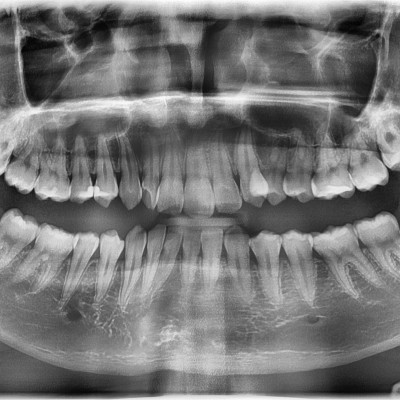

#18사랑니 발치 + #19 과잉치발치 #18사랑니 발치 + #19 과잉치발치 구강 외과 전문의가 당일 발치했습니다. ---------------..

작성자 이턱이 작성일 02-10 조회 51